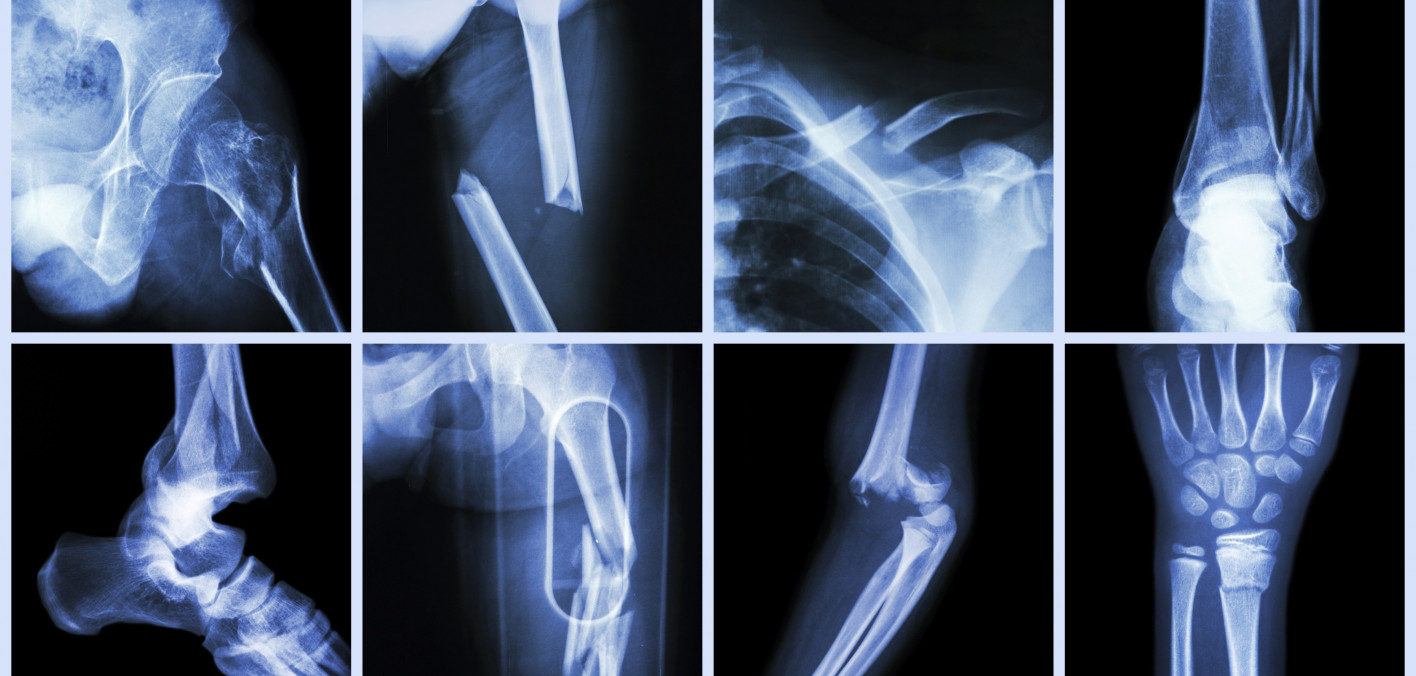

Higher Risk of Bone fracture among People Living with HIV iesResearch Hiv And Bone Loss Certain lifestyle factors, hormonal changes, and comorbidities that increase the risk of bone loss are prevalent in patients with hiv. Hiv infection and certain hiv medicines may increase the risk of osteoporosis, amplifying the increased risk in older adults,. Both the fracture risk assessment tool (frax) and measurement of bone mineral density (bmd) via a dexa scan are routinely used. Hiv And Bone Loss.

Study People with HIV at Increased Risk of Bone Fractures Hiv And Bone Loss Hiv infection and certain hiv medicines may increase the risk of osteoporosis, amplifying the increased risk in older adults,. We provide guidance and recommendations on clinically relevant questions regarding the screening, monitoring, and. Both the fracture risk assessment tool (frax) and measurement of bone mineral density (bmd) via a dexa scan are routinely used in the assessment. Certain lifestyle factors,. Hiv And Bone Loss.

Central Clinical School News Blog People with HIV face higher risk of Hiv And Bone Loss Hiv infection and certain hiv medicines may increase the risk of osteoporosis, amplifying the increased risk in older adults,. We provide guidance and recommendations on clinically relevant questions regarding the screening, monitoring, and. Both the fracture risk assessment tool (frax) and measurement of bone mineral density (bmd) via a dexa scan are routinely used in the assessment. Certain lifestyle factors,. Hiv And Bone Loss.